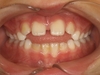

Palais étroit

Palais étroit avec déviation de la mâchoire inférieure et du menton

Un palais étroit peut entraîner une déviation de la mâchoire inférieure et du menton, causant des problèmes de mastication et potentiellement une croissance asymétrique. Il est par ailleurs le plus souvent associé à un défaut d’espace pour l’évolution des dents définitives supérieures, et lié à une position de langue basse associée à une respiration par la bouche.

Pourquoi traiter ?

Un traitement précoce permet de recentrer la mâchoire inférieure et de permettre aux dents définitives d’évoluer normalement. Le rétablissement d’une fermeture efficace des lèvres, d’une respiration nasale et d’une bonne position de la langue est le garant d’une croissance harmonieuse des mâchoires, et participe à la bonne santé générale de l’enfant.

Palais étroit et manque de place pour l'évolution des dents définitives supérieures

Un palais étroit peut entraîner un manque de place pour l'éruption des incisives définitives supérieures, pouvant conduire à une évolution des incisives latérales en arrière des incisives centrales (et donc souvent en inversé d’occlusion avec les dents du bas), voire à une inclusion des canines définitives. Il est par ailleurs le plus souvent lié à une position de langue basse associée à une respiration par la bouche.

Un traitement précoce permet l’évolution normale des dents définitives. Par ailleurs, l’élargissement du palais permet de faciliter le rétablissement d’une respiration nasale et d’une bonne position de la langue, garantes d’une croissance harmonieuse des mâchoires, et participant à la bonne santé générale de l’enfant.